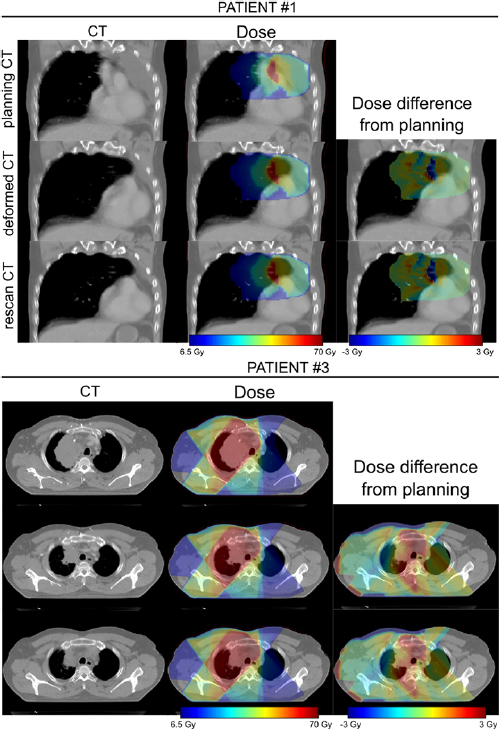

The dCT images were well-matched to the rCT images and the associated dose distributions for each patient were visually indistinguishable from the rCT gold standards (figure 6).

Figure 6. Comparison of rCT and dCT CT scans and dose distributions (against pCT) for two of the patients included in the study. In each case the prescription dose was 64 Gy.

Download figure:

Standard image High-resolution imageThe results of the voxelwise dose difference analysis for the two selected regions are presented at figure 7.

Figure 7. Boxplots showing the distribution of voxelwise dose differences for each patient for the TV (treated volume—region exceeding 95% of the prescribed dose) and the HDRV (high dose region volume—region exceeding 50% but less than 95% of the prescribed dose). Outliers corresponding to points outside the ±2.7 s.d. range have been suppressed.

Download figure:

The CTV data suggests there was a reduction in target coverage early on in the treatment with V99% for the original CTV structure dropping from 96.2% to 92.7% in Week 1. Dose distributions as calculated on the pCT and the Week 1 dCT are shown at figure 10.

Figure 10. (Top) dose distributions calculated on the pCT and week 1 dCT and (bottom) dCT DVHs overlaid with the pCT DVHs.

Download figure:

Standard image High-resolution imageA reduction in GTV size is evident on visual inspection of the two images. As a result, the proportion of soft tissue present within the original CTV volume was less on the Week 1 dCT image than on the pCT image. As soft tissue absorbs dose to a greater extent than lung tissue, V99% coverage of the original CTV structure was correspondingly reduced. Unlike the original CTV structure, the deformed CTV reflected the reduction in GTV size, which meant that V99% coverage for this structure only reduced to 94.8%.

While these results demonstrate the type of quantitative information that may be derived from our method, it is important to note that neither the original, nor deformed, CTV is representative of the actual clinical CTV at that point in time and they should not be relied on as such. What these structures can do, however, is provide information to the clinician to assist in the outlining of an appropriate CTV for dose evaluation. This is discussed further in the section below.

Due to the proximity of the target volume to the spinal canal there was a clear risk that anatomical change would cause this volume to breach the clinical tolerance (47 Gy < 0.1 cc). Table 4 includes data for both the spinal canal and the spinal canal PRV structure (spinal canal + 5 mm) which suggests that, while the PRV structure breached tolerance in both Week 2 (Dmax = 57.1 Gy) and Week 3 (Dmax = 58.8 Gy), the spinal canal volume itself remained well within tolerance. This information would prove useful to the clinician in deciding if a replan is necessary. Other OAR structures remained well below tolerance (Lung V20 < 30%, Heart V40 < 30%).